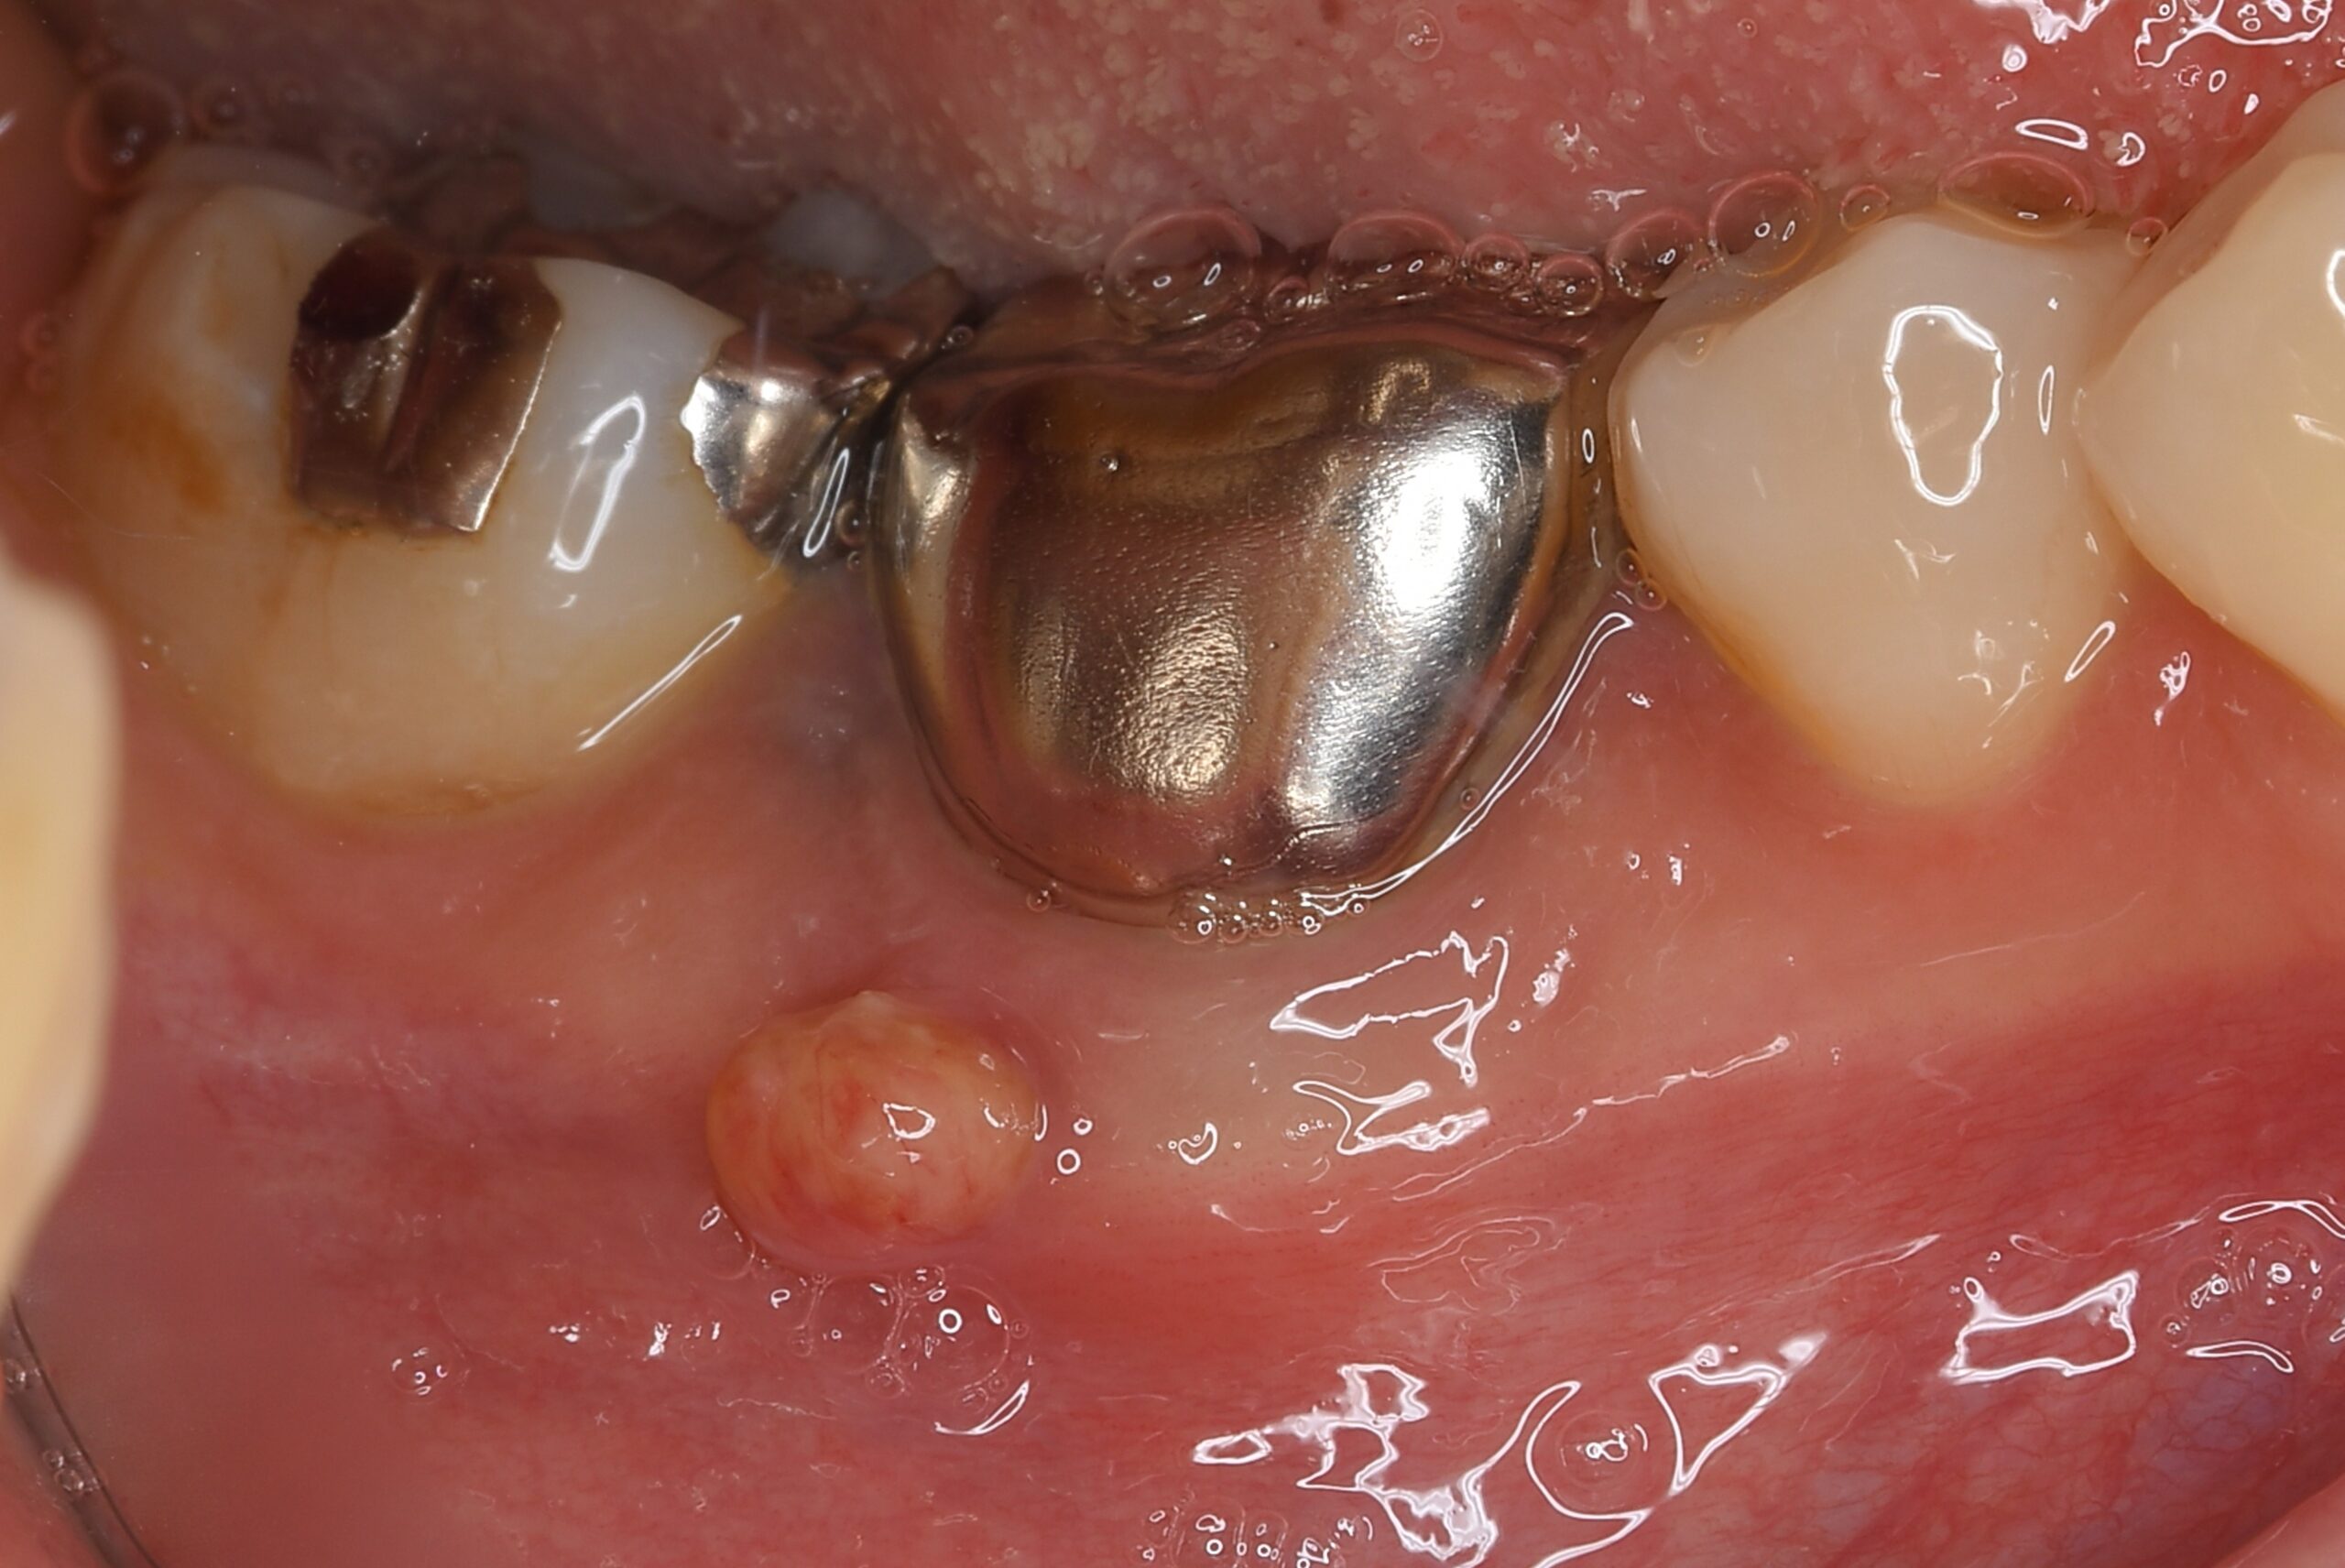

症例1:パーフォレーションリペア症例

(歯の中に大きな穴が空いてしまっているのを埋めて再生を促す治療)

歯に穴が空いていて骨に炎症がある状態 |

CTでも歯の周囲に骨がないのが分かる。 |

BEFORE |

AFTER |

人為的根穿孔を起こした部分に感染を起こしており、歯周ポケットが9㎜ありました。 ラバーダム防湿とマイクロスコープを使用して丁寧に治療を行いました。 殺菌性があり歯を補強することのできるMTAという根管充填材料を使用して、歯周ポケットは2㎜に改善しました。 |